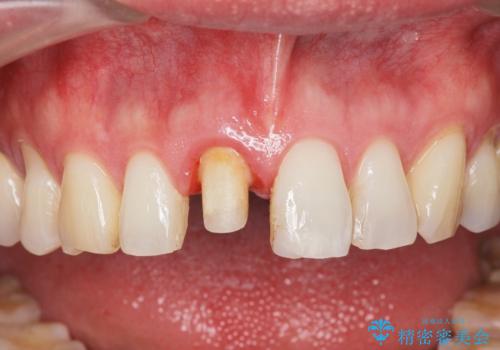

- 15.4万円(仮歯・ファイバーコア・ジルコニアクラウン)費用は治療当時の料金となります